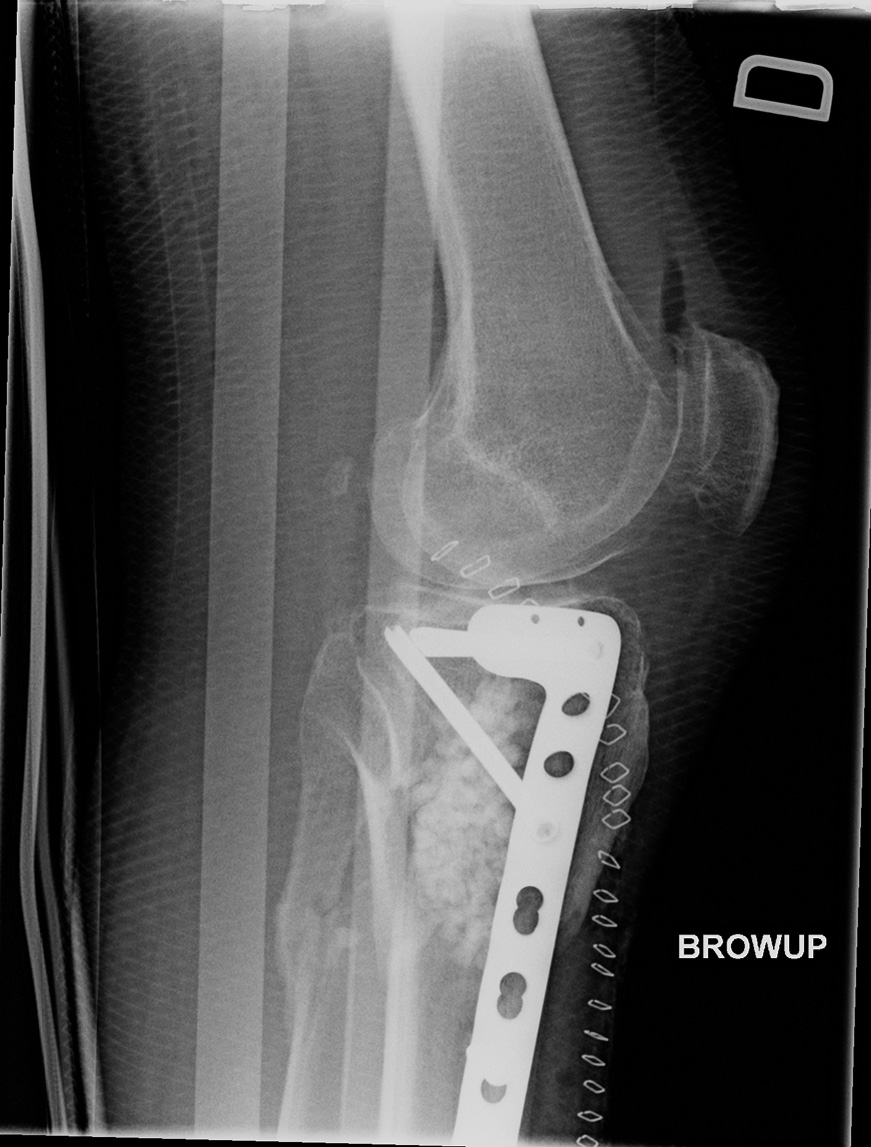

64-year-old male:

Postoperative control of a Schatzker type 6 tibial plateaux fracture.

Locked plate and screws

Open reduction of a Schatzker type 6 fracture and fixation with a locked plate and screws on the lateral side of the tibia.

Decreased lateral joint space and a 12° valgus alignment.

Bone graft

Bone graft installed during the surgical procedure.

Sling

Splint in place.

Fibular fracture

The fibular fracture was not addressed.

Metallic staples

Staples for the surgical incision closure.